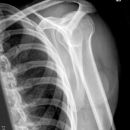

Subcapitale Fraktur und Tuberculum majus